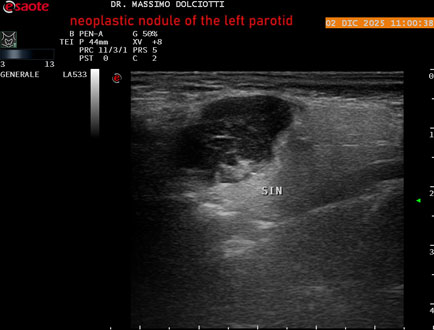

Data inserimento: 18/12/2025

Ecografia del: 02/12/2025

Strumento: Esaote MyLab Eight

Sonda: Lineare Multifrequenza 3-13 MHz

Età Paziente: F 70 anni

Motivazione dell'esame: tumefazione ed arrossamento in sede parotidea sinistra, nel 2003 k mammella sinistra operata e sottoposta a radio e chemioterapia.

Commento all'esame: le immagini ed il video documentano, alla parotide destra, nodulo ipoecogeno, a margini irregolari e frastagliati, con vascolarizzazione ad alto indice di resistenza, da ricondurre a nodulo neoplastico da tipizzare.

Conclusioni: nodulo neoplastico alla parotide sinistra (neoplastic nodule in the left parotid gland).